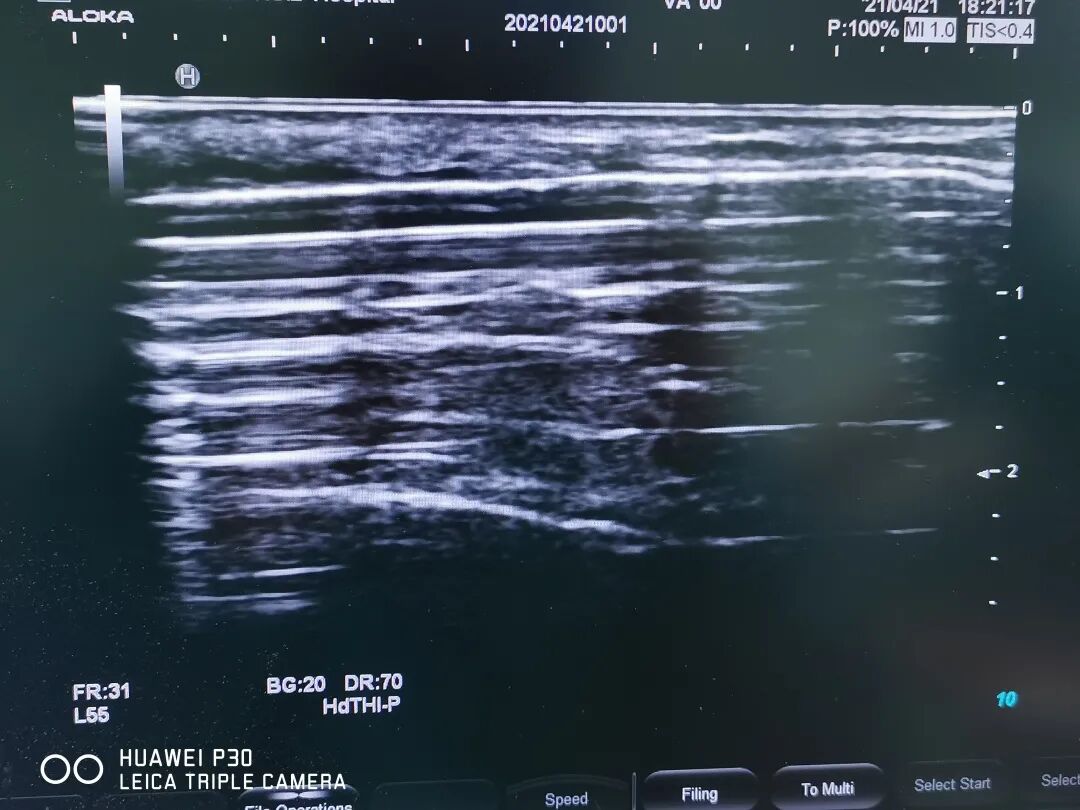

患者術(shù)后

▲球囊擴(kuò)張血彩

理解和信任往往會激發(fā)力量創(chuàng)造奇跡,在超聲科、麻醉科的通力協(xié)助下,雖然術(shù)中碰到一些問題,但都被一一解決,手術(shù)很成功,術(shù)后第二天,內(nèi)瘺穿刺上機(jī),血流量達(dá)到260ml/min,保住了寶貴的生命線,避免了置管!